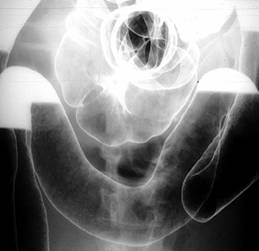

Leziunile endoscopice precoce sunt reprezentate de ulceratiile aftoide. In evolutie apar ulceratii de forma si talie diferita (serpiginoase, in harta geografica sau rotunde). In stadiile avansate apare aspectul caracteristic de "piatra de pavaj" datorita ulceratiilor profunde, confluente, care delimiteaza intre ele insule de mucoasa non-ulcerata. La colonoscopie mai pot fi stenoze frecvent ulcerate. Distributia segmentara, discontinua si asimetrica a leziunilor este o caracteristica endoscopica a bolii Crohn.

Ulceratii aftoide Ulcer map-like, cu stenoza Aspect "piatra de pavaj"

Localizarea leziunilor este exclusiv la nivelul intestinului subtire in 25-30% din cazuri, ileo-colica in 40-50% din cazuri si strict colonica in 15-25 % din cazuri, in special la batrani. Localizarea perianala (fisuri, fistule, abcese, supuratii perirectale) apare in peste 50% din cazuri. In 0,5- 4 % din cazuri pot fi afectate segmentele proximale ale tractului digestiv (cavitatea bucala, esofag, stomac, duoden). Foarte rar boala se poate localiza la apendice.